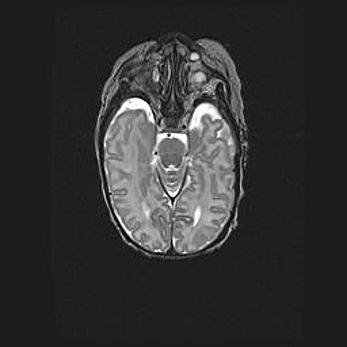

Сообщающаяся гидроцефалия. Кистозная энцефаломаляция головного мозга.

Возраст: 3 месяца 4 дня

Вес: 3100 г

Пол: женский

Окружность головы: 34 см

Срок гестации: 31 неделя

Кистозная энцефаломаляция головного мозга - одна из форм поражения головного мозга в детском возрасте. Характеризуется возникновением множественных и распространённых кист в коре, белом веществе и подкорковых образованиях головного мозга у плодов, новорождённых и детей раннего возраста. Развитие кистозной энцефаломаляции связано с внутриутробной асфиксией и гипотонией, родовой травмой, тромбозом синусов, пороками развития сосудов, инфекциями, сепсисом и другими причинами. Наиболее значимые инфекционные агенты: вирусы простого герпеса, цитомегалии, краснухи, токсоплазмы, энтеробактерии, золотистый стафилококк и другие.